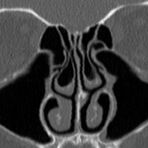

Kopf

• Nasennebenhöhlen (Entzündungen, Tumore)